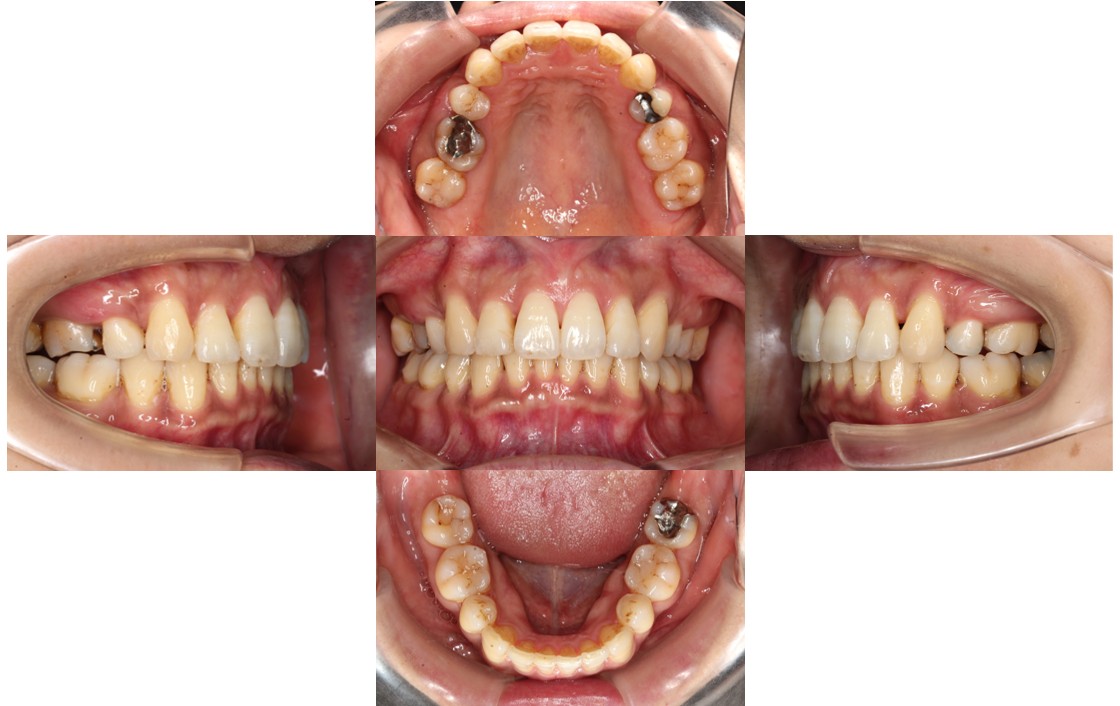

2年経過の口腔内の状態です。

上下ともに前歯がガタガタしていた部分が改善し、口元も下がりかみ合わせが良くなったとご満足いただけました。

| 年齢層 | 30代 |

| 主訴 | 上の歯が出ている、下の歯の凸凹、かみ合わせ改善 |

| 治療費用 | 検査・診断:税込38,500円/裏側矯正治療(リンガル矯正):税込1,397,000円 |

| 治療期間 | 約2年(31回) |

| 抜歯 | 有(【上顎】両側4番 【下顎】両側5番) |

| 矯正の装置 | 裏側矯正(舌側矯正) |

| 副作用、リスク | 歯肉退縮,歯根吸収,疼痛,咬合の違和感,装置の違和感,虫歯,歯肉炎 |